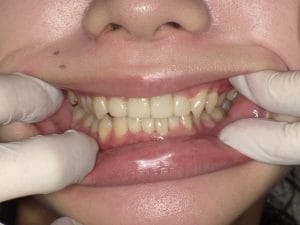

Case033

前歯が虫歯なのと、保険のプラスチックで大きく治療されていて色が悪いこと、歯並びが出っ歯気味であることを気にしてセラミックにしたいという主訴で来院された患者様です。

虫歯が大きかったところは神経治療をきちんと行い、

初診時を含めてトータル4回のご来院で完了です。

今回は前歯を下げる、歯列を整える、白すぎず自然に綺麗に見える色というご希望に沿って治療しました。

ご興味のある方はいつでもご相談ください。

担当 理事長 佐藤 悠野